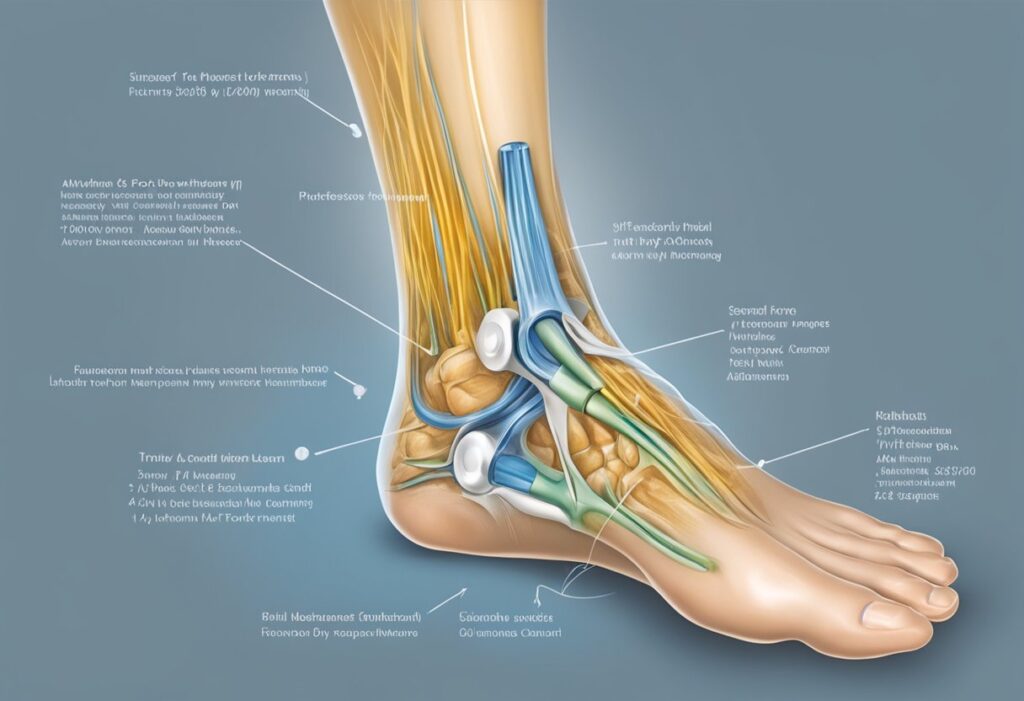

Caracterizada pela perda temporária ou permanente de sensibilidade, essa sensação incômoda pode ser causada por diversos fatores, desde problemas circulatórios até condições neurológicas mais complexas.

Dormência no pé é um sintoma que se caracteriza pela sensação de falta de sensibilidade ou formigamento nos pés.

É uma condição que pode ocorrer em um ou nos dois pés, e pode ser causada por diversos fatores.

Problemas vasculares, como má circulação ou problemas com a artéria que irriga o pé, também podem causar dormência no pé.

Quando a circulação é prejudicada, os nervos dos pés podem não receber o suprimento adequado de sangue e oxigênio, o que pode resultar em dormência e outros sintomas.